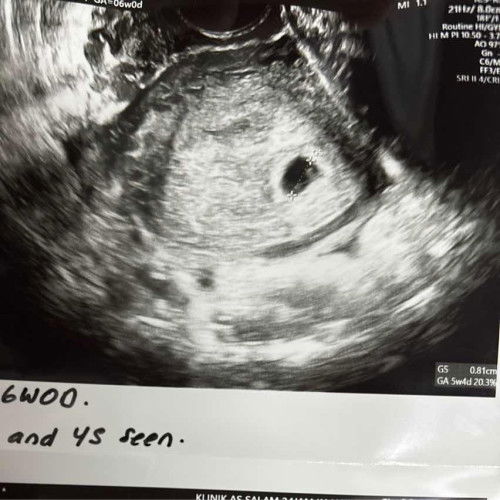

Saya dah call banyak kali klinik kesihatan kwsn saya. Ada yg sy baru cakap hello dia letak. Waktu lain dia kata nurse kawasan sy keluar melawat ibu dekat rumah, sia suruh call petang. Bila call petang dia tak balik lagi. Lepas tu katanya esok nurse tu call sy. Dah 2 minggu mcm ni. Masalahnya sy dengar nurse tu berbual sesama sendiri: Nurse 1: Budak yg minggu lepas tu call lagi sekali. Nurse 2: Awal lagi baru 7 minggu nak bukak buku pink. Biasanya org bukak buku pink masa 8 minggu kan? Sy minggu depan masuk kerja, kalau time off lebih 2 jam dikira sbg half day. Kenapa tak boleh bukak awal seminggu? Susahnya lah. Husband kata kalau mcm tu bukak je buku pink lambat sikit, 10w ke 12w ke. Tapi tak ada masalah ke kalau sy tak makan ubat2 mengandung obimin calcium etc tu skrg? Tak apa ke klau 12w baru sy start makan? #SeriusTanya #ingintahu